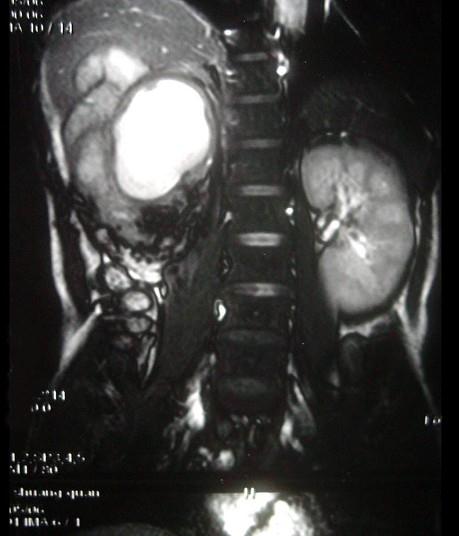

问题 女,43岁,右腰部疼痛不适2年余,加重3天,CT及MR检查如图,应诊断为 ( )

选项 A、右肾脂肪肉瘤 B、右肾海绵状血管瘤 C、右肾错构瘤合并出血 D、右肾脂肪瘤 E、右肾癌

答案 C